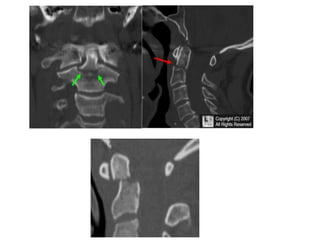

• CT thin cuts with reconstruction ( sagittal, Coronal )

Radiological Assessment • Cervical–X- Ray Lateral A-P especially (( Odontoid # type 2 )) Open mouth • CT thin cuts with reconstruction ( sagittal, Coronal ) • MRI

C1

C1 fracture